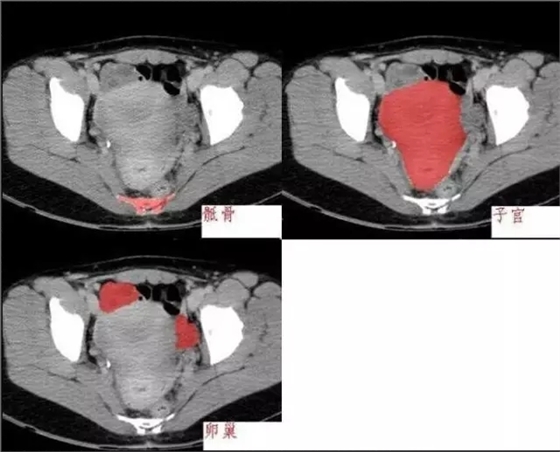

640.webp (2).jpg